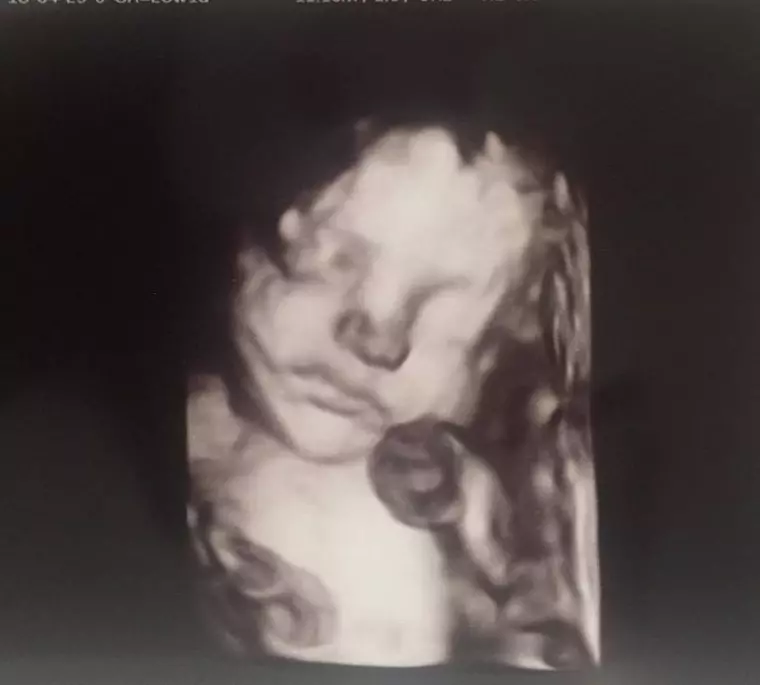

Roxana Ciuhulescu naşte prin cezariană al doilea copil. În curând, vedeta va deveni mamă pentru a doua oară. În exclusivitate pentru VIVA!, Roxana ne-a povestit cum se pregăteşte pentru venirea pe lume a băieţelului şi ce semnificaţie au cele două prenume pe care le va purta!

Împreună cu soţul său, cu Silviu Bulugioiu, au ales şi numele micuţului: Cezar Ioan. În cadrul interviului, ea ne-a dezvăluit şi semnificaţia prenumelor, dar şi faptul că va naşte prin cezariană la sfatul medicului. Viitorul tătic are de gând chiar să asiste în sala de naştere.

„Foarte bine mă simt. Sunt în trimestrul al doilea de sarcină, mai am opt săptămâni şi un pic până nasc. Sper să nu se întâmple mai devreme, să duc sarcina până la termen. Mă simt grozav. Am fost dimineaţă la sport. (…) La prima sarcină am făcut chiar până în ultima zi. Mi se pare ciudat că lumea mă priveşte într-un fel…cum faci sport? Încerc să explic că sunt gravidă, nu sunt bolnavă. (…) Am cumpărat deja mobilierul, deşi nu am apucat să aduc nimic încă acasă. Acum trebuie să facem modificările, să mutăm, să facem schimbări în camera bebeluşului pentru că înainte aveam altă mobilă. (…) El are curaj să intre în sala de naştere şi chiar am vorbit cu doctoriţa Cezara Bucur cu care eu voi naşte. Acum sper să nu leşine, i-am zis să nu facă vreo figură acolo”, ne-a spus vedeta în exclusivitate.